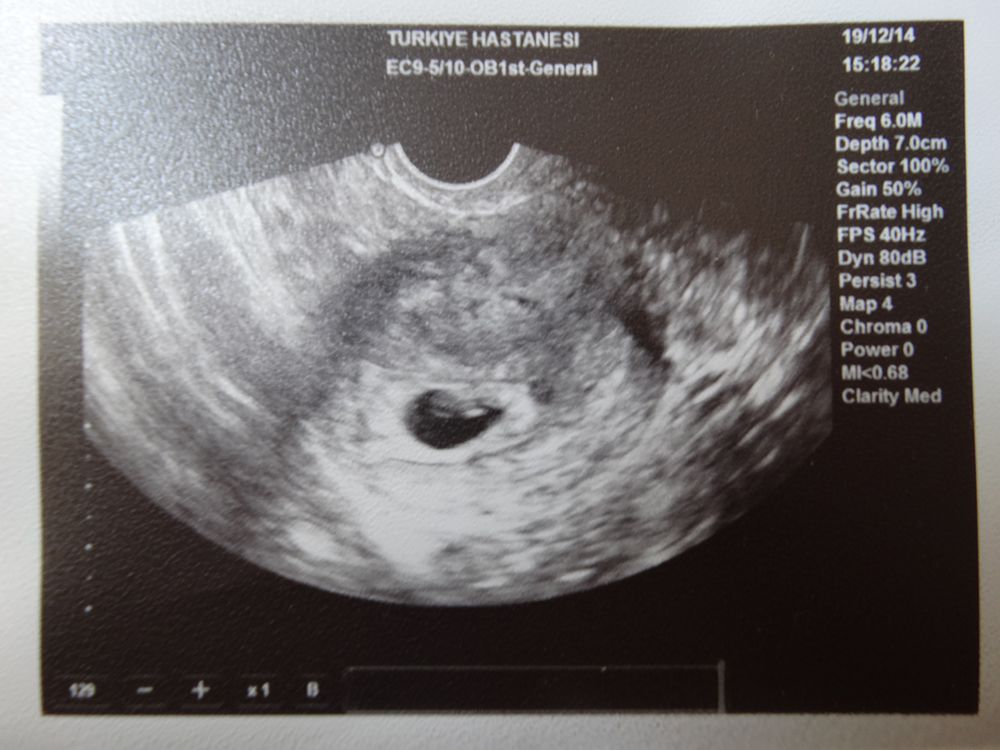

Опасность замершей беременности в том, что она может долго не проявляться. Если будущая мать регулярно посещает врача, то диагностика замершей беременности не представляет труда, гибель плодного яйца можно будет заподозрить из-за несоответствия размеров матки срокам, а УЗИ на 7 неделе беременности позволит поставить точный диагноз.

Сердце уже сокращается и перегоняет кровь по телу, образуется перегородка, которая делит его на две камеры. Продолжается развитие кровеносных сосудов. Расположено сердце пока посреди грудины и немного выпячивается вперед, но через некоторое время оно займет свое естественное положение. С помощью аппарата УЗИ уже можно услышать сердцебиение будущего малыша, частота ударов которого составляет 150-160 в минуту. Не стоит беспокоиться, что сердцебиение плода учащено – это связано с нынешним этапом его развития.

Беременность на данном сроке уже должна проходить под наблюдением специалиста, можно сделать 6-7 недель беременности УЗИ, врач обязательно назначит сдачу разнообразных анализов (анализ на определение уровня ХГЧ в моче, анализы на ВИЧ и сифилис, ОАК и ОАМ, мазок из влагалища, в некоторых случаях — гемастазиограмму).